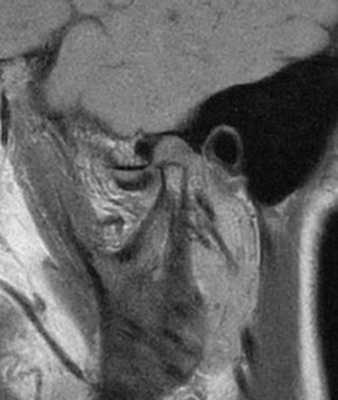

Фото 3. МРТ-скан левого ВНЧС при закрытом состоянии рта: визуализация переднего смещения диска без редукции.

Фото 4. МРТ-скан левого ВНЧС при закрытом состоянии рта: визуализация переднего смещения диска без редукции.